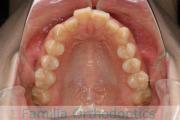

でこぼこと口元が出ている横顔が気になるとのことで来院されました。重度の叢生(ガタガタ)と側方へのズレがあるため、アンカースクリューを併用したマルチブラケット法にて治療を行いました。3年弱、35回程度の通院をしていただきました。叢生が強いため、部分的にガタガタが再発・後戻りするリスクが高いケースでした。

- ≫治療後

上顎

下顎

前歯の関係など

右側

正面

左側